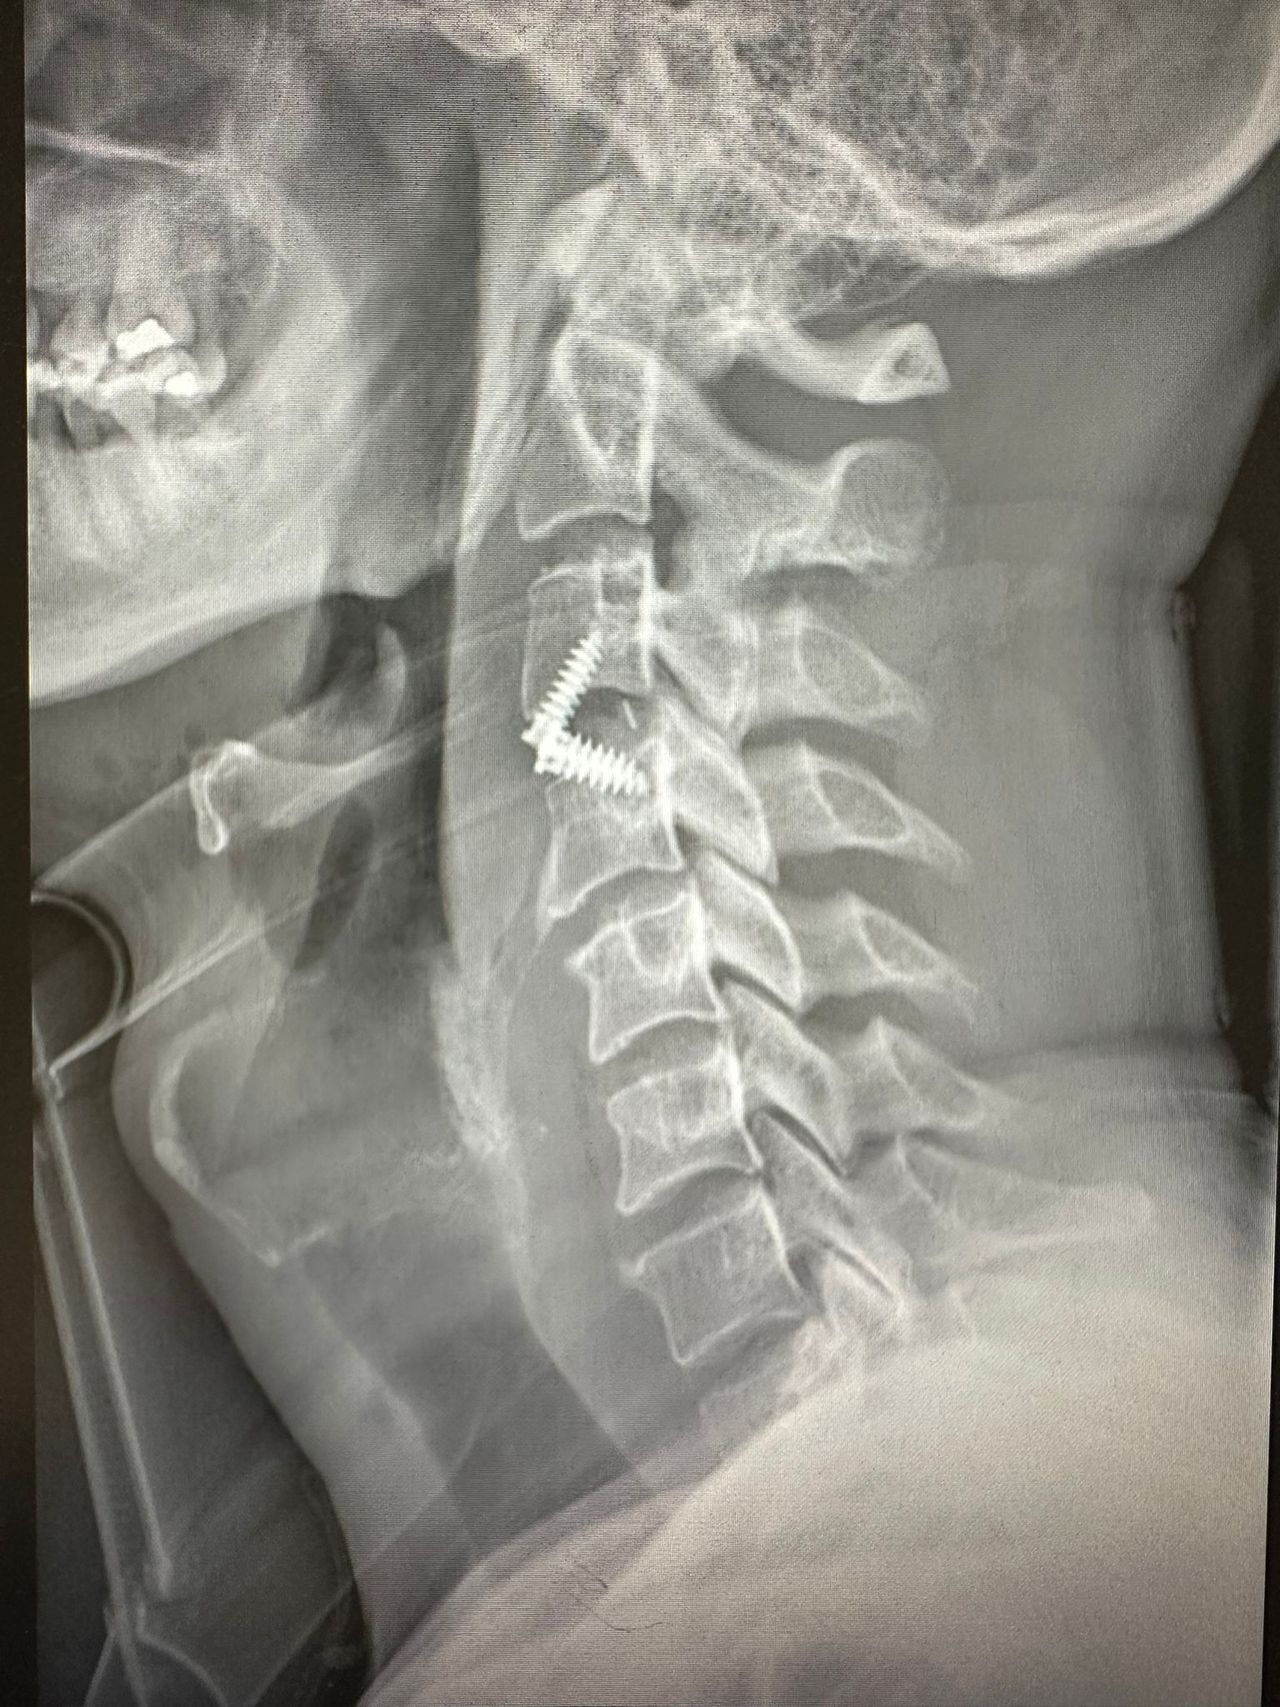

- Chirurgia Mininvasiva percutanea vertebrale - stabilizzazioni e artrodesi intersomatiche (per fratture vertebrali, spondilolistesi, instabilità vertebrali, discopatie)

- RX scopia intraoperatoria